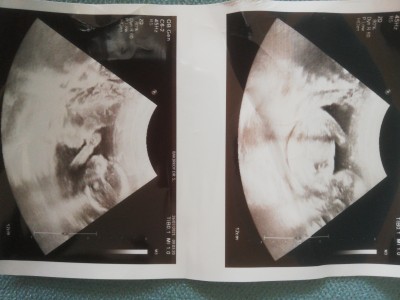

Ultrasondan anlayanlar rica etsem cinsiyet tahmini yapabilir mi

17 haftalık

Yandan çekmiş nasıl belli olcak popodan olması lazım bence

Yan duruyor bebek belli olmaz bu şekilde

Doktorun anlamadığını burdan anlamak zor biraz :)